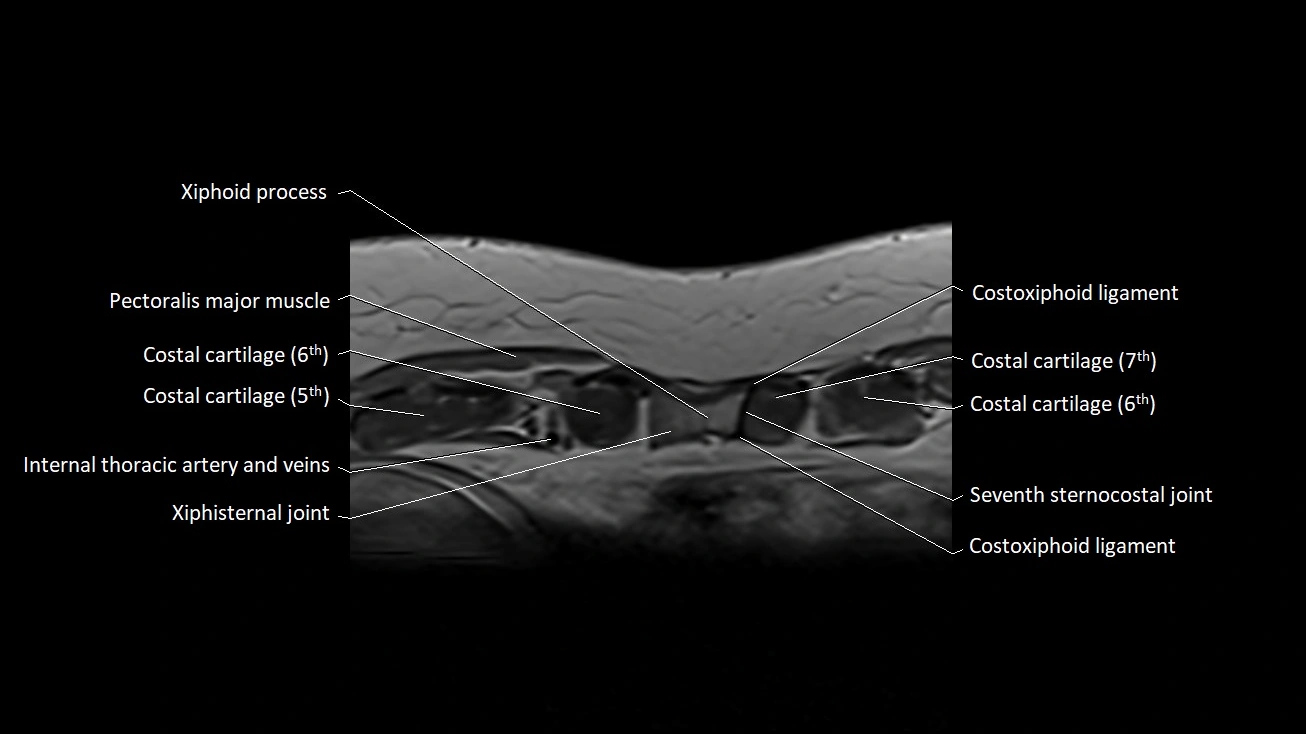

MRI images

image